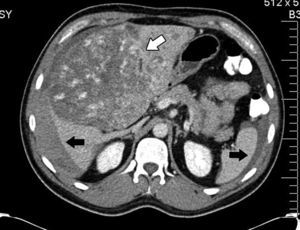

En septiembre presentó hemoptisis y disnea, por lo que se hospitalizo en medio hospitalario particular, en donde se le realizó tomografía axial computada de tórax (fig. 2), broncoscopia con toma de cultivos y biopsias, los cuales fueron negativos a malignidad, tuberculosis o infección fúngica. Se solicita tomografía axial computada de abdomen simple y contrastada donde se muestran lesiones múltiples, redondeadas, hipodensas en el injerto hepático (fig. 3); se toma biopsia guiada por tomografía axial computada, que se reporta negativa a malignidad.

Se realizó autopsia, en la cual se observan tumoraciones redondeadas, vascularizadas en todo el injerto hepático, afectación a porta y arteria hepática (fig. 4), en parénquima pulmonar, múltiples metástasis las cuales forman lesiones pequeñas, con datos hemorrágicos (fig. 5). Además también presentaba metástasis en el bazo, glándulas suprarrenales y páncreas.